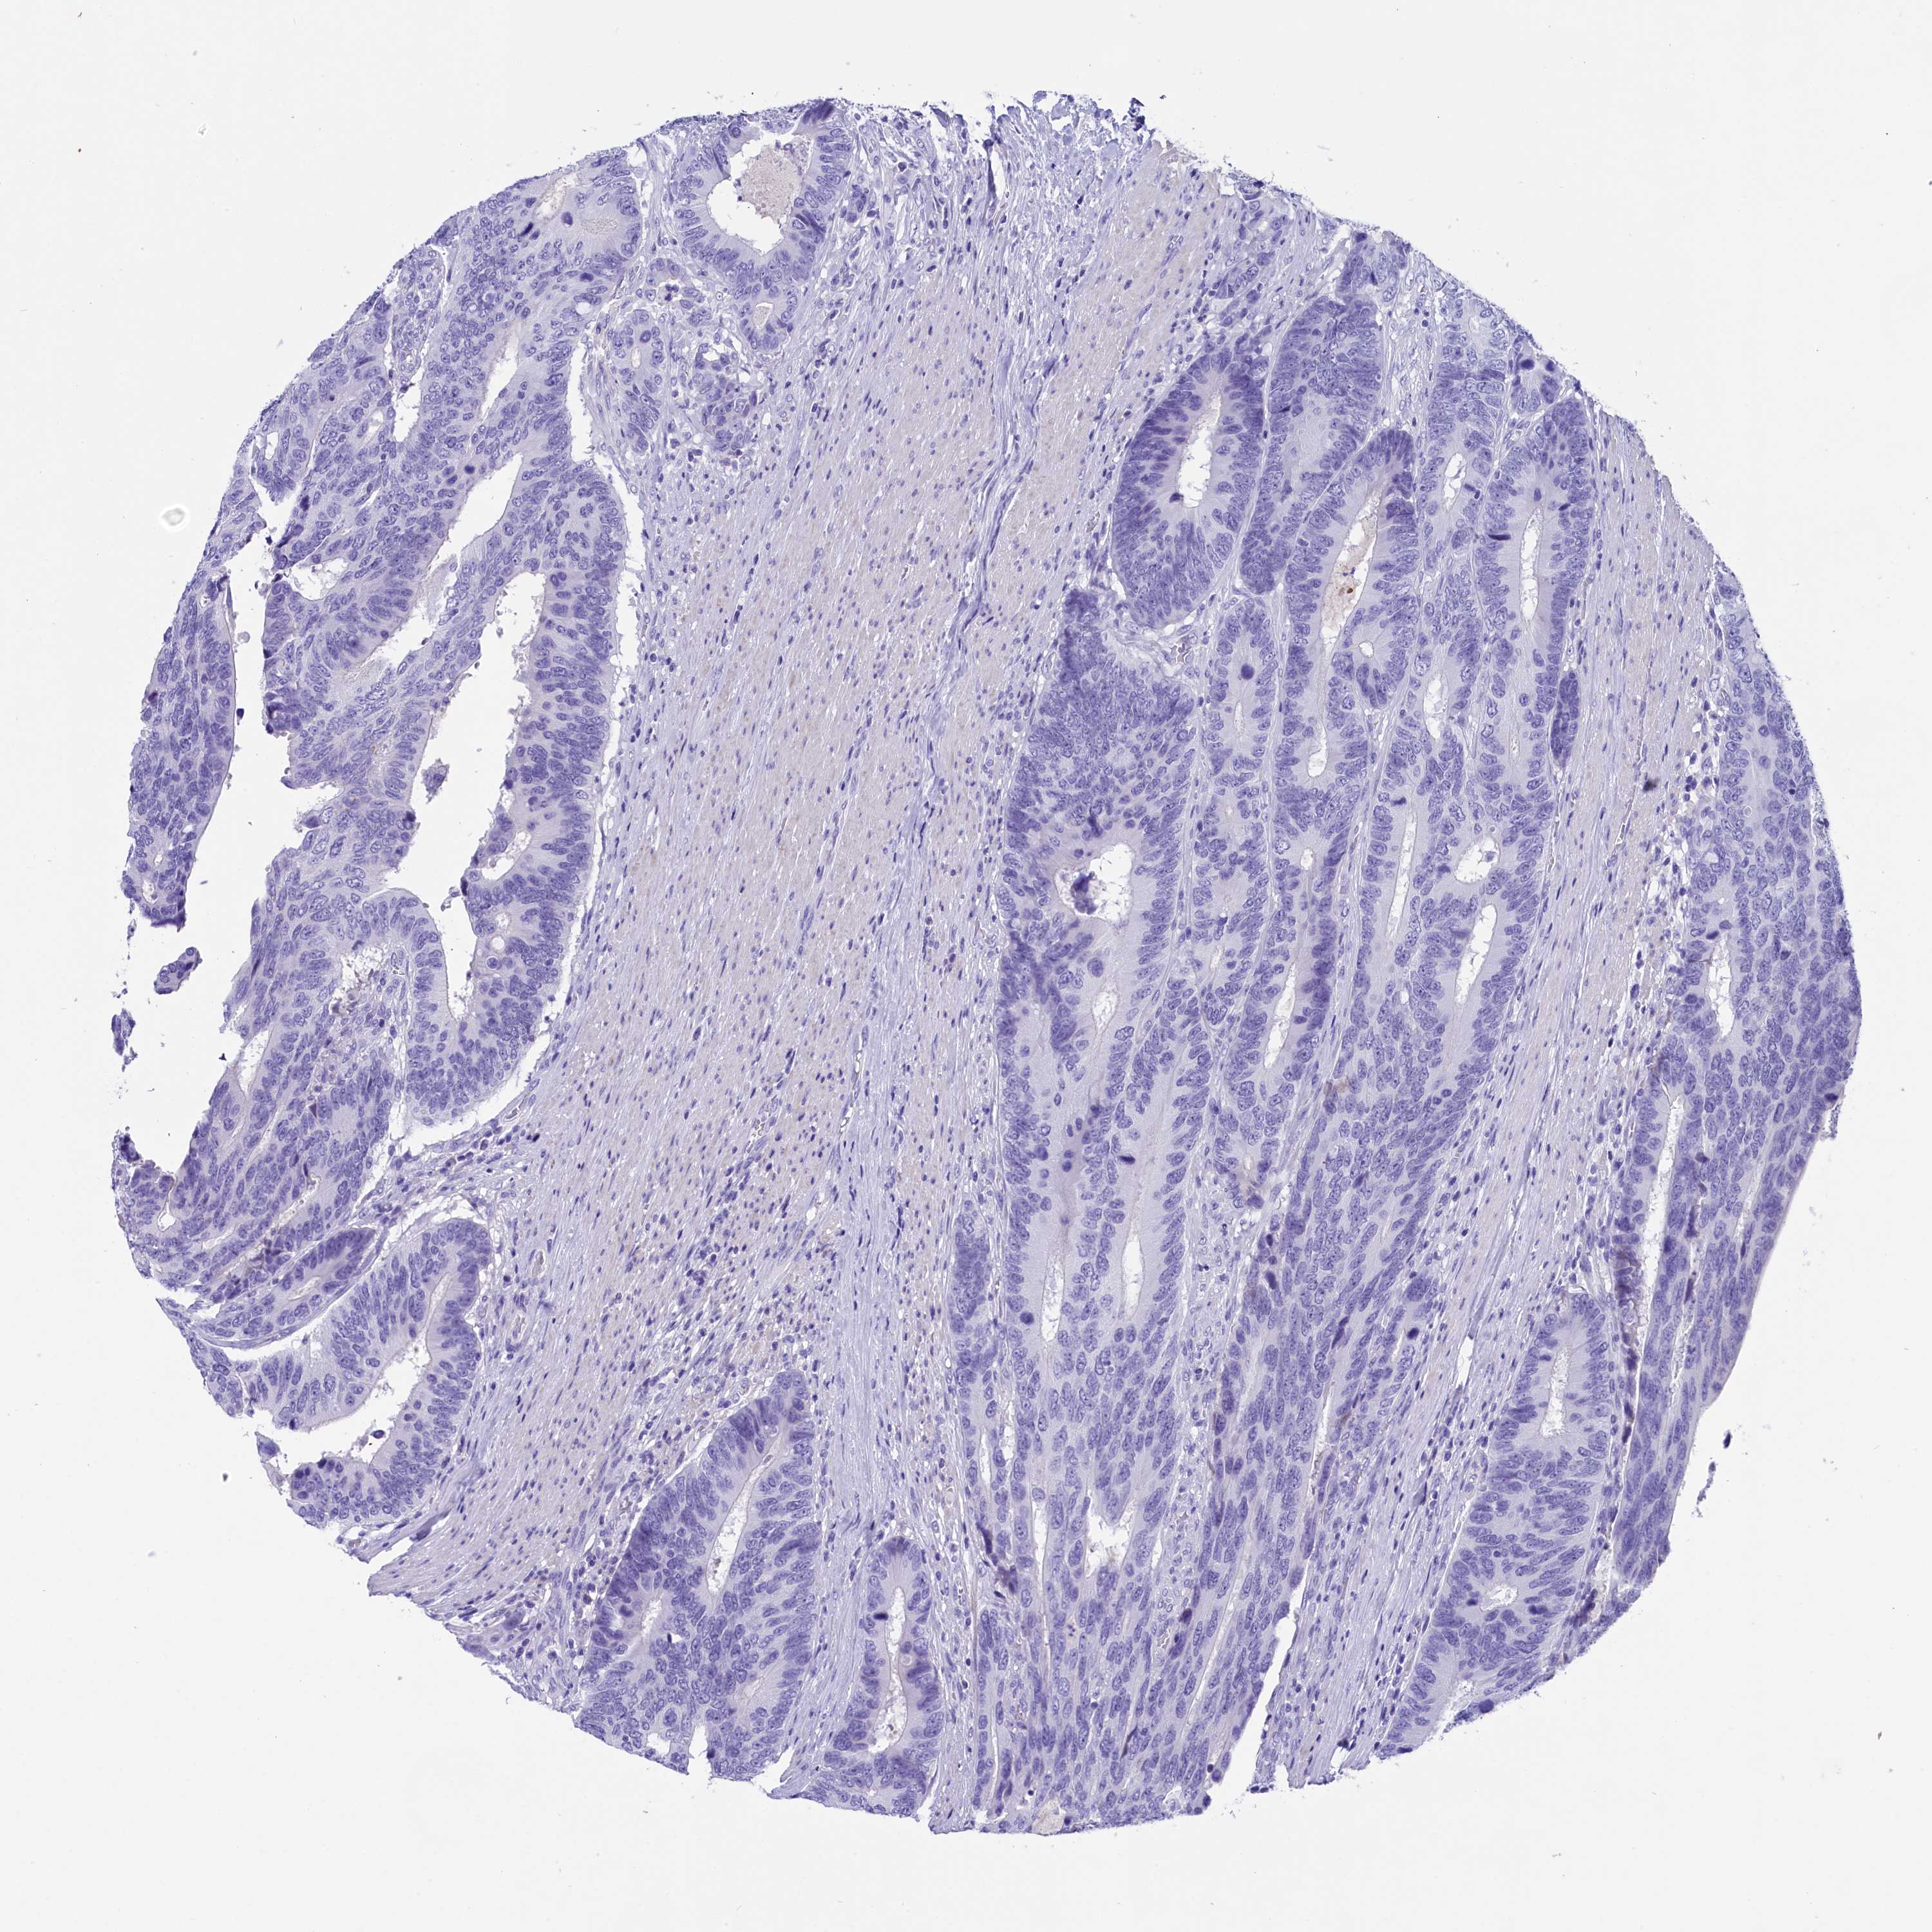

CANCER COLORECTAL CANCER Show tissue menu

Colorectal cancer

Human cancer

Colon adenocarcinoma